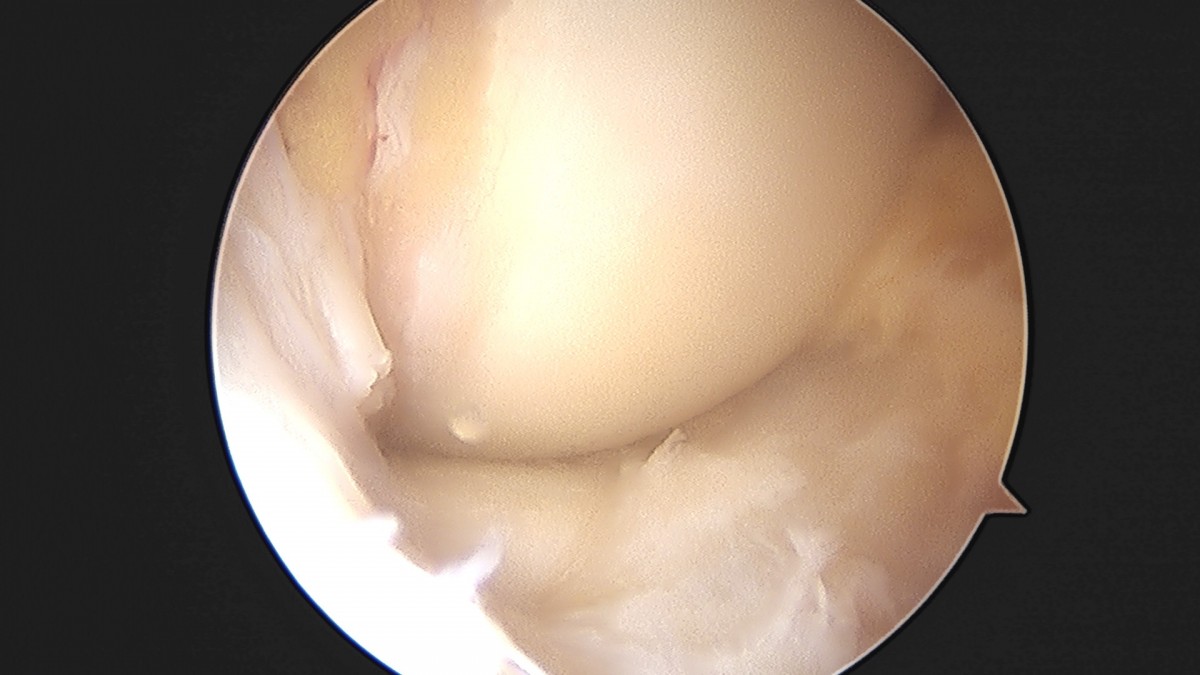

이재상원장님 무릎 반월상 연골판 절제술 조미O 환자

작성자 최고관리자 댓글 0건 조회 368회 작성일 25-09-16 16:01